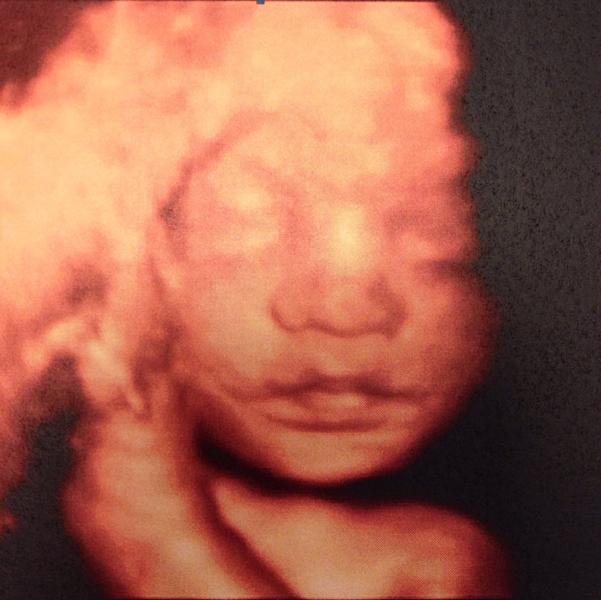

а теперь о нас))) У Тимона все замечательно!!! 39 см, 1600гр. абсолютно все в норме😀 лежит правильно, обвития нет. моя плацента поднялась и теперь в норме : 5 см от края (и сказала еще поднимется, была в краевом предлежании). еще раскрыта тайна моего большого пузика - умеренное многоводие ( сказала это не страшно, а мылышу это удобно- мес...